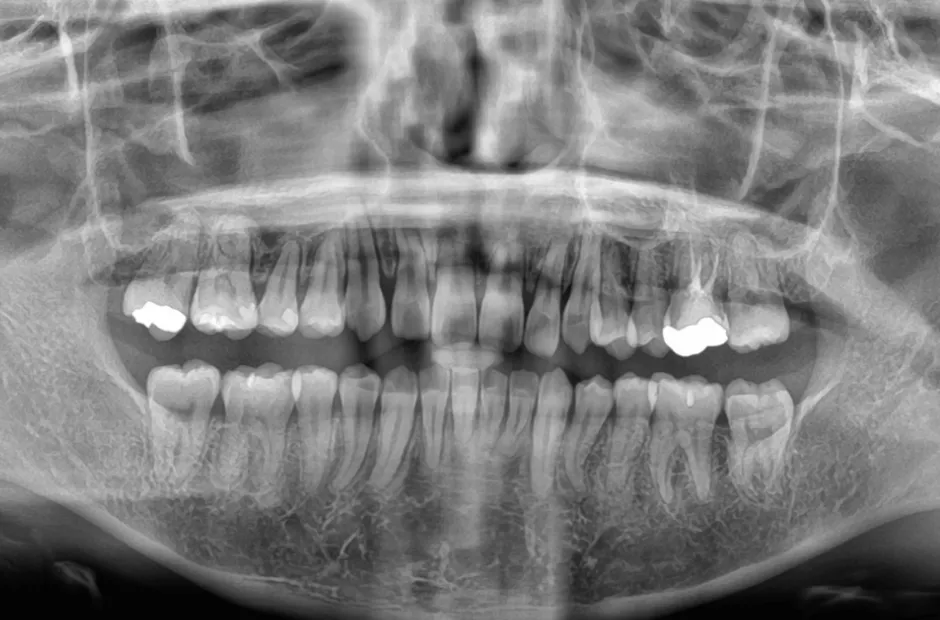

| 診断名・主訴 | 下顎前突、叢生 |

|---|---|

| 年齢・性別 | 23歳・女性 |

| 治療期間・回数 | 3年 |

| 治療に用いた主な装置 | 上顎5,5 下顎4,4 |

| 抜歯部位 | 舌側矯正 |

| 治療費 | 100万円(税抜) |

| リスク・副作用 | 装置による違和感・疼痛・歯肉退縮・歯根吸収・虫歯のリスクなど |

治療後